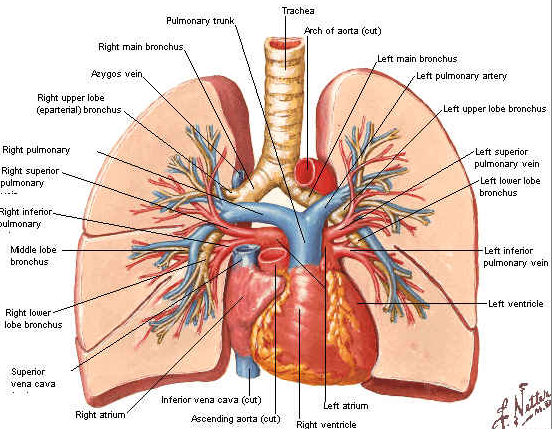

BOLILE APARATULUI CARDIO-VASCULAR

BOLILE APARATULUI CARDIO-VASCULAR Aparatul cardio-vascular este format din inima, vase sanguine si limfatice. Inima este un organ tetracameral (doua atrii si doua ventricule), care pompeaz�Citeste tot ... 820 cuvinte

Dimensiune mica

+ cu imagini |

ANEVRISM SACCIFORM DE CROSA AORTICA LA UN PACIENT ASIMPTOMATIC SI PROBLEMELE DE CONDUITA TERAPEUTICA

ANEVRISM SACCIFORM DE CROSA AORTICA LA UN PACIENT ASIMPTOMATIC SI PROBLEMELE DE CONDUITA TERAPEUTICA Definitie: Anevrismul de aorta reprezinta dilatarea aortei de peste 1,5 ori diametrul aortei corespunzator segmentului respectCiteste tot ... 1147 cuvinte

Dimensiune mica

+ cu imagini |